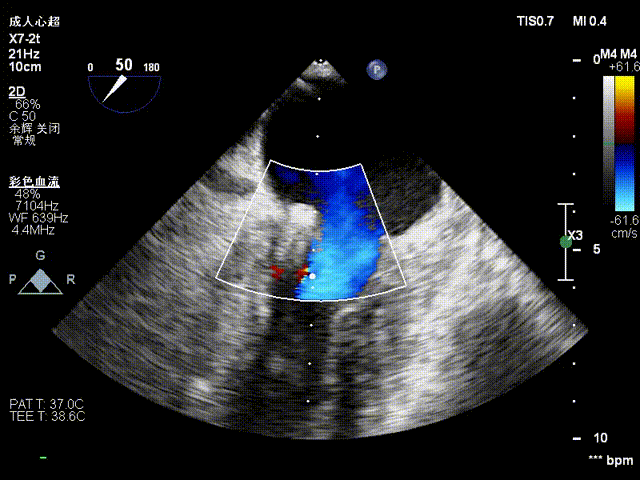

房间隔穿刺

NeoNova®C6(宽6mm)夹合器沿输送系统进入左房,调整夹合器orientation,夹合器抵达3区反流处。

进夹合器

进夹合器调弹道